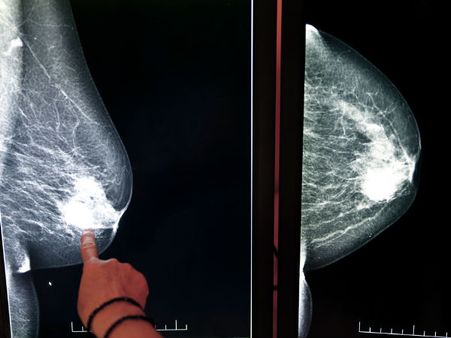

World Cancer Day: স্তন ক্যান্সারের ঝুঁকি রোধ করবেন কীভাবে? দেখে নিন কিছু উপায়

প্রতিবছর ৪ ফেব্রুয়ারি বিশ্ব ক্যান্সার দিবস পালন করা হয়। মারণ রোগ ক্যান্সারের বিরুদ্ধে বিশ্ব জুড়ে সচেতনতা প্রচার করতে এই দিবস উদযাপন করা হয়। বিশ্বব্যাপী স্তন ক্যান্সার মহিলাদের মধ্যে সবচেয়ে সাধারণ একটি ক্যান্সার। যখন স্তনের কিছু কোষ অস্বাভাবিকভাবে বেড়ে যায়, তখন ওই অনিয়মিত ও অতিরিক্ত কোষগুলো বিভাজনের মাধ্যমে টিউমার বা পিণ্ডে পরিণত হয়।

৯) প্রতি মাসে স্ক্রিনিং করা

স্তন ক্যান্সার স্ক্রিনিংয়ের মাধ্যমে স্তন ক্যান্সারের প্রাথমিক পর্যায় সনাক্ত হতে পারে। স্ক্রিনিং স্তন ক্যান্সারের প্রাথমিক পর্যায়ে প্রতিরোধে সহায়তা করতে পারে যা, এর চিকিৎসা করা আরও সহজ করে তোলে।

স্তন ক্যান্সারের ঝুঁকি রোধের উল্লিখিত উপায়গুলি ছাড়াও, প্রতিদিন নিজের স্তন নিজেই পরীক্ষা করা গুরুত্বপূর্ণ, ত্বকের কোনও পরিবর্তন বা কোনও পিণ্ড হয়েছে কি না। আপনি যদি আপনার স্তনে কোনওরকম অস্বাভাবিক পরিবর্তন লক্ষ্য করেন, তাহলে দেরি না করে অবিলম্বে একজন চিকিৎসকের সঙ্গে পরামর্শ করুন।